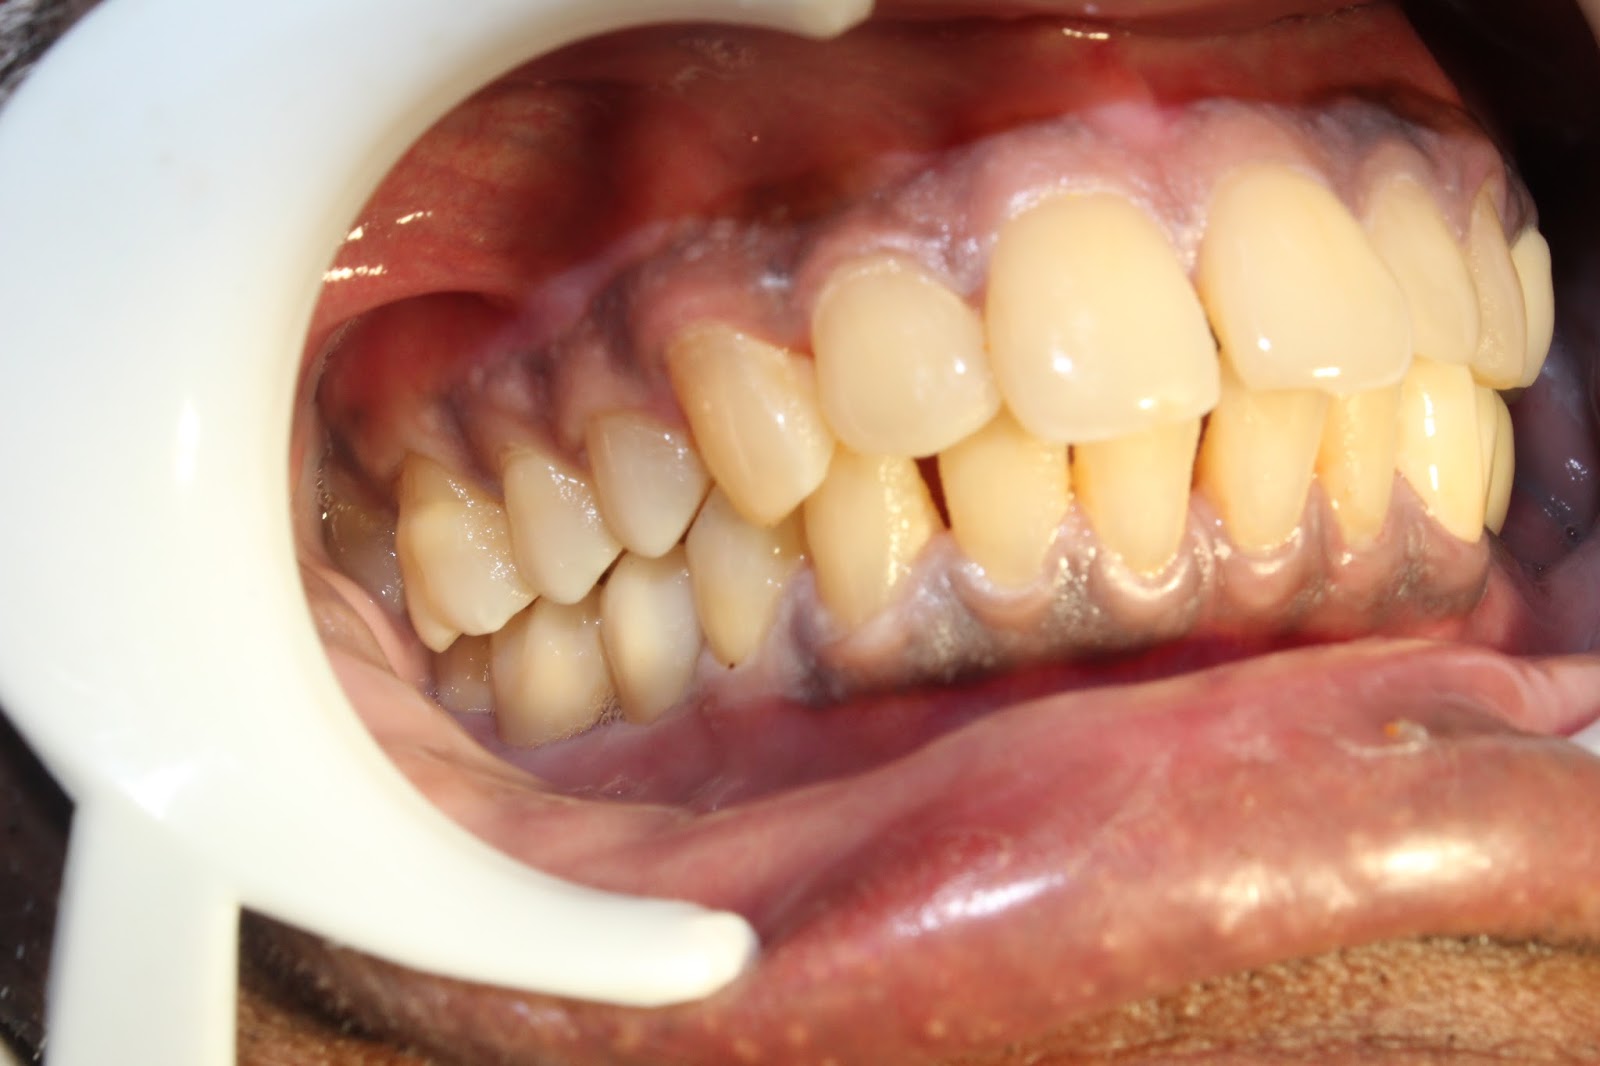

Before fixing the zirconium bridge ...upon dental implant abutments- right side

Before fixing the zircon bridge - left side

After cementation of zirconium bridge on right lower molar region...

After cementation of zirconium bridge on left side -lower jaw